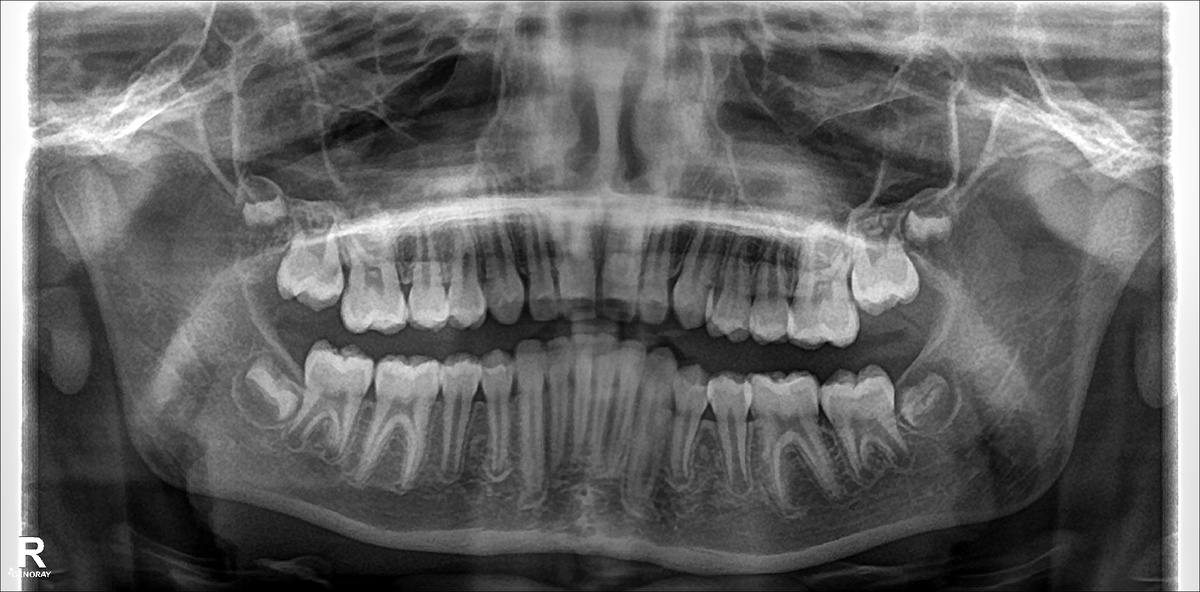

У многих людей челюсть слишком мала, чтобы вместить все зубы. Зачатки «восьмёрок» начинают давить на вторые моляры, провоцируя скученность передних зубов и тормозя движение при лечении брекетами.

• скученность зубов;

• давление на соседние зубы сзади;

• замедление ортодонтического лечения.

Поэтому современные ортодонты рекомендуют удалять зачатки зубов мудрости ещё до их прорезывания.

Не всегда. Решение принимает ортодонт и хирург после диагностики. Если на снимке видно, что «восьмёрки» растут неправильно и будут мешать, врач рекомендует удаление.